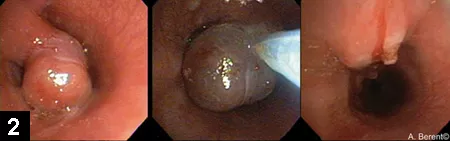

Figure 2. Tracheal polyp in a dog during endoscopic polypectomy

Because tracheal tumors are often located in the intrathoracic trachea, surgical removal via resection and anastomosis can be associated with significant morbidity. However, polypoid masses (eg, tracheal polyp [Figure 2]), extra­medullary plasmacytoma, leiomyoma/leiomyosarcoma) can be effectively resected by using electrocautery snares during biopsy, allowing concurrent diagnosis and treatment. If the mass is broad based and not amenable to polypectomy, a laser (diode or CO<sub2sub>) or stent can help open the airway. Tracheal stents are safe, are highly effective, can be placed quickly, and can be useful in treating nonresectable masses.